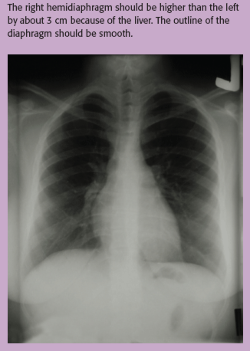

The diaphragm is dome-shaped and has the same density as water. The right hemidiaphragm should be higher than the left because of the liver. (See Visualizing the diaphragm.)The difference should be only about 3 cm. The outline of the diaphragm should be smooth.8

Figure. Visualizing ... - Click to enlarge in new windowFigure. Visualizing the diaphragm